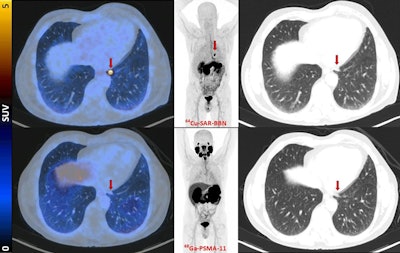

Fused PET/CT, maximum-intensity projection PET, and lung-windowed CT images (from left to right) from Cu-64 SAR-BBN (top row) and Ga-68 PSMA-11 (bottom row) PET/CT study of patient demonstrating left subpleural lesion (arrows, SUVmax of 10 at 1 hour) that showed Cu-64 SAR-BBN uptake but no Ga-68 PSMA-11 uptake. PSA was 1.84 ng/mL at time of imaging. This patient underwent lobectomy, with histopathology demonstrating metastatic prostate cancer.Image courtesy of the Journal of Nuclear Medicine

According to the findings, Cu-64 SAR-BBN-avid disease was identified in 44% (11/25) of participants. Of patients with positive Cu-64 SAR-BBN PET/CT results, 37% (3/11) had prostate bed recurrence, 46% (5/11) had pelvic node disease, and 27% (3/11) had distant disease (lung and bone).